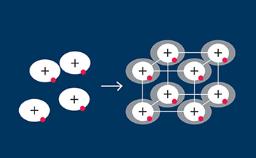

- outline recommendations for configuration of implants supporting a complete overdenture

- identify the degree of prosthesis support according to implant configuration

- select appropriate attachment types for denture retention